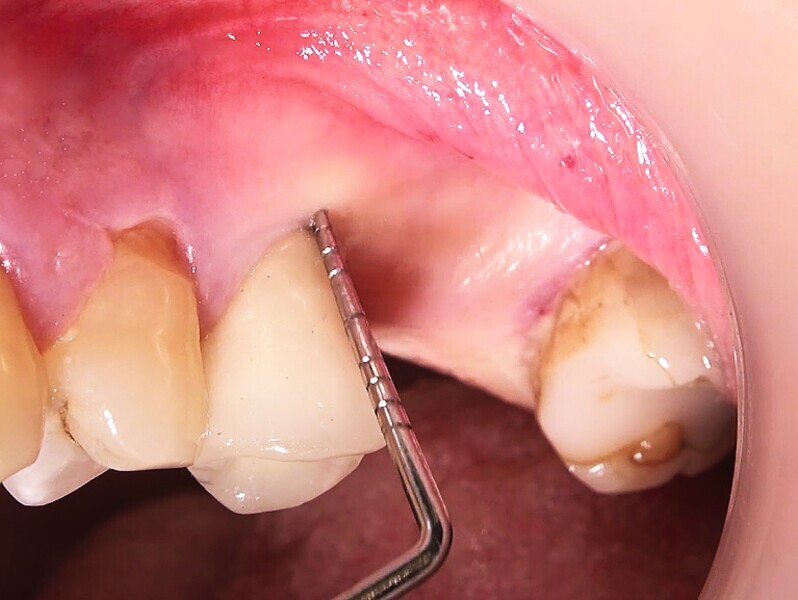

Fig. 35 : Région molaire édentée avant l’implantation.

Fig. 36 : Région molaire édentée avant l’implantation.

Un patient présentant un défaut infraosseux s’est présenté au cabinet dentaire avec le souhait explicite d’un traitement par un implant en zircone, pour remplacer l’une de ses molaires. Un implant deux pièces en zircone a donc été posé et le défaut infra-osseux a été traité dans le même temps, au moyen d’une allogreffe osseuse et du dérivé de matrice amélaire Emdogain (Straumann). La mise en charge n’a pas été réalisée à ce stade (Figs. 35–45).